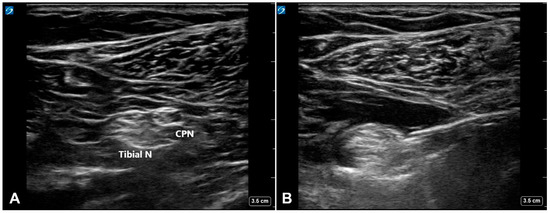

2. Materials and Methods